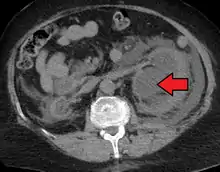

Massive hydronephrosis as marked by the arrow.